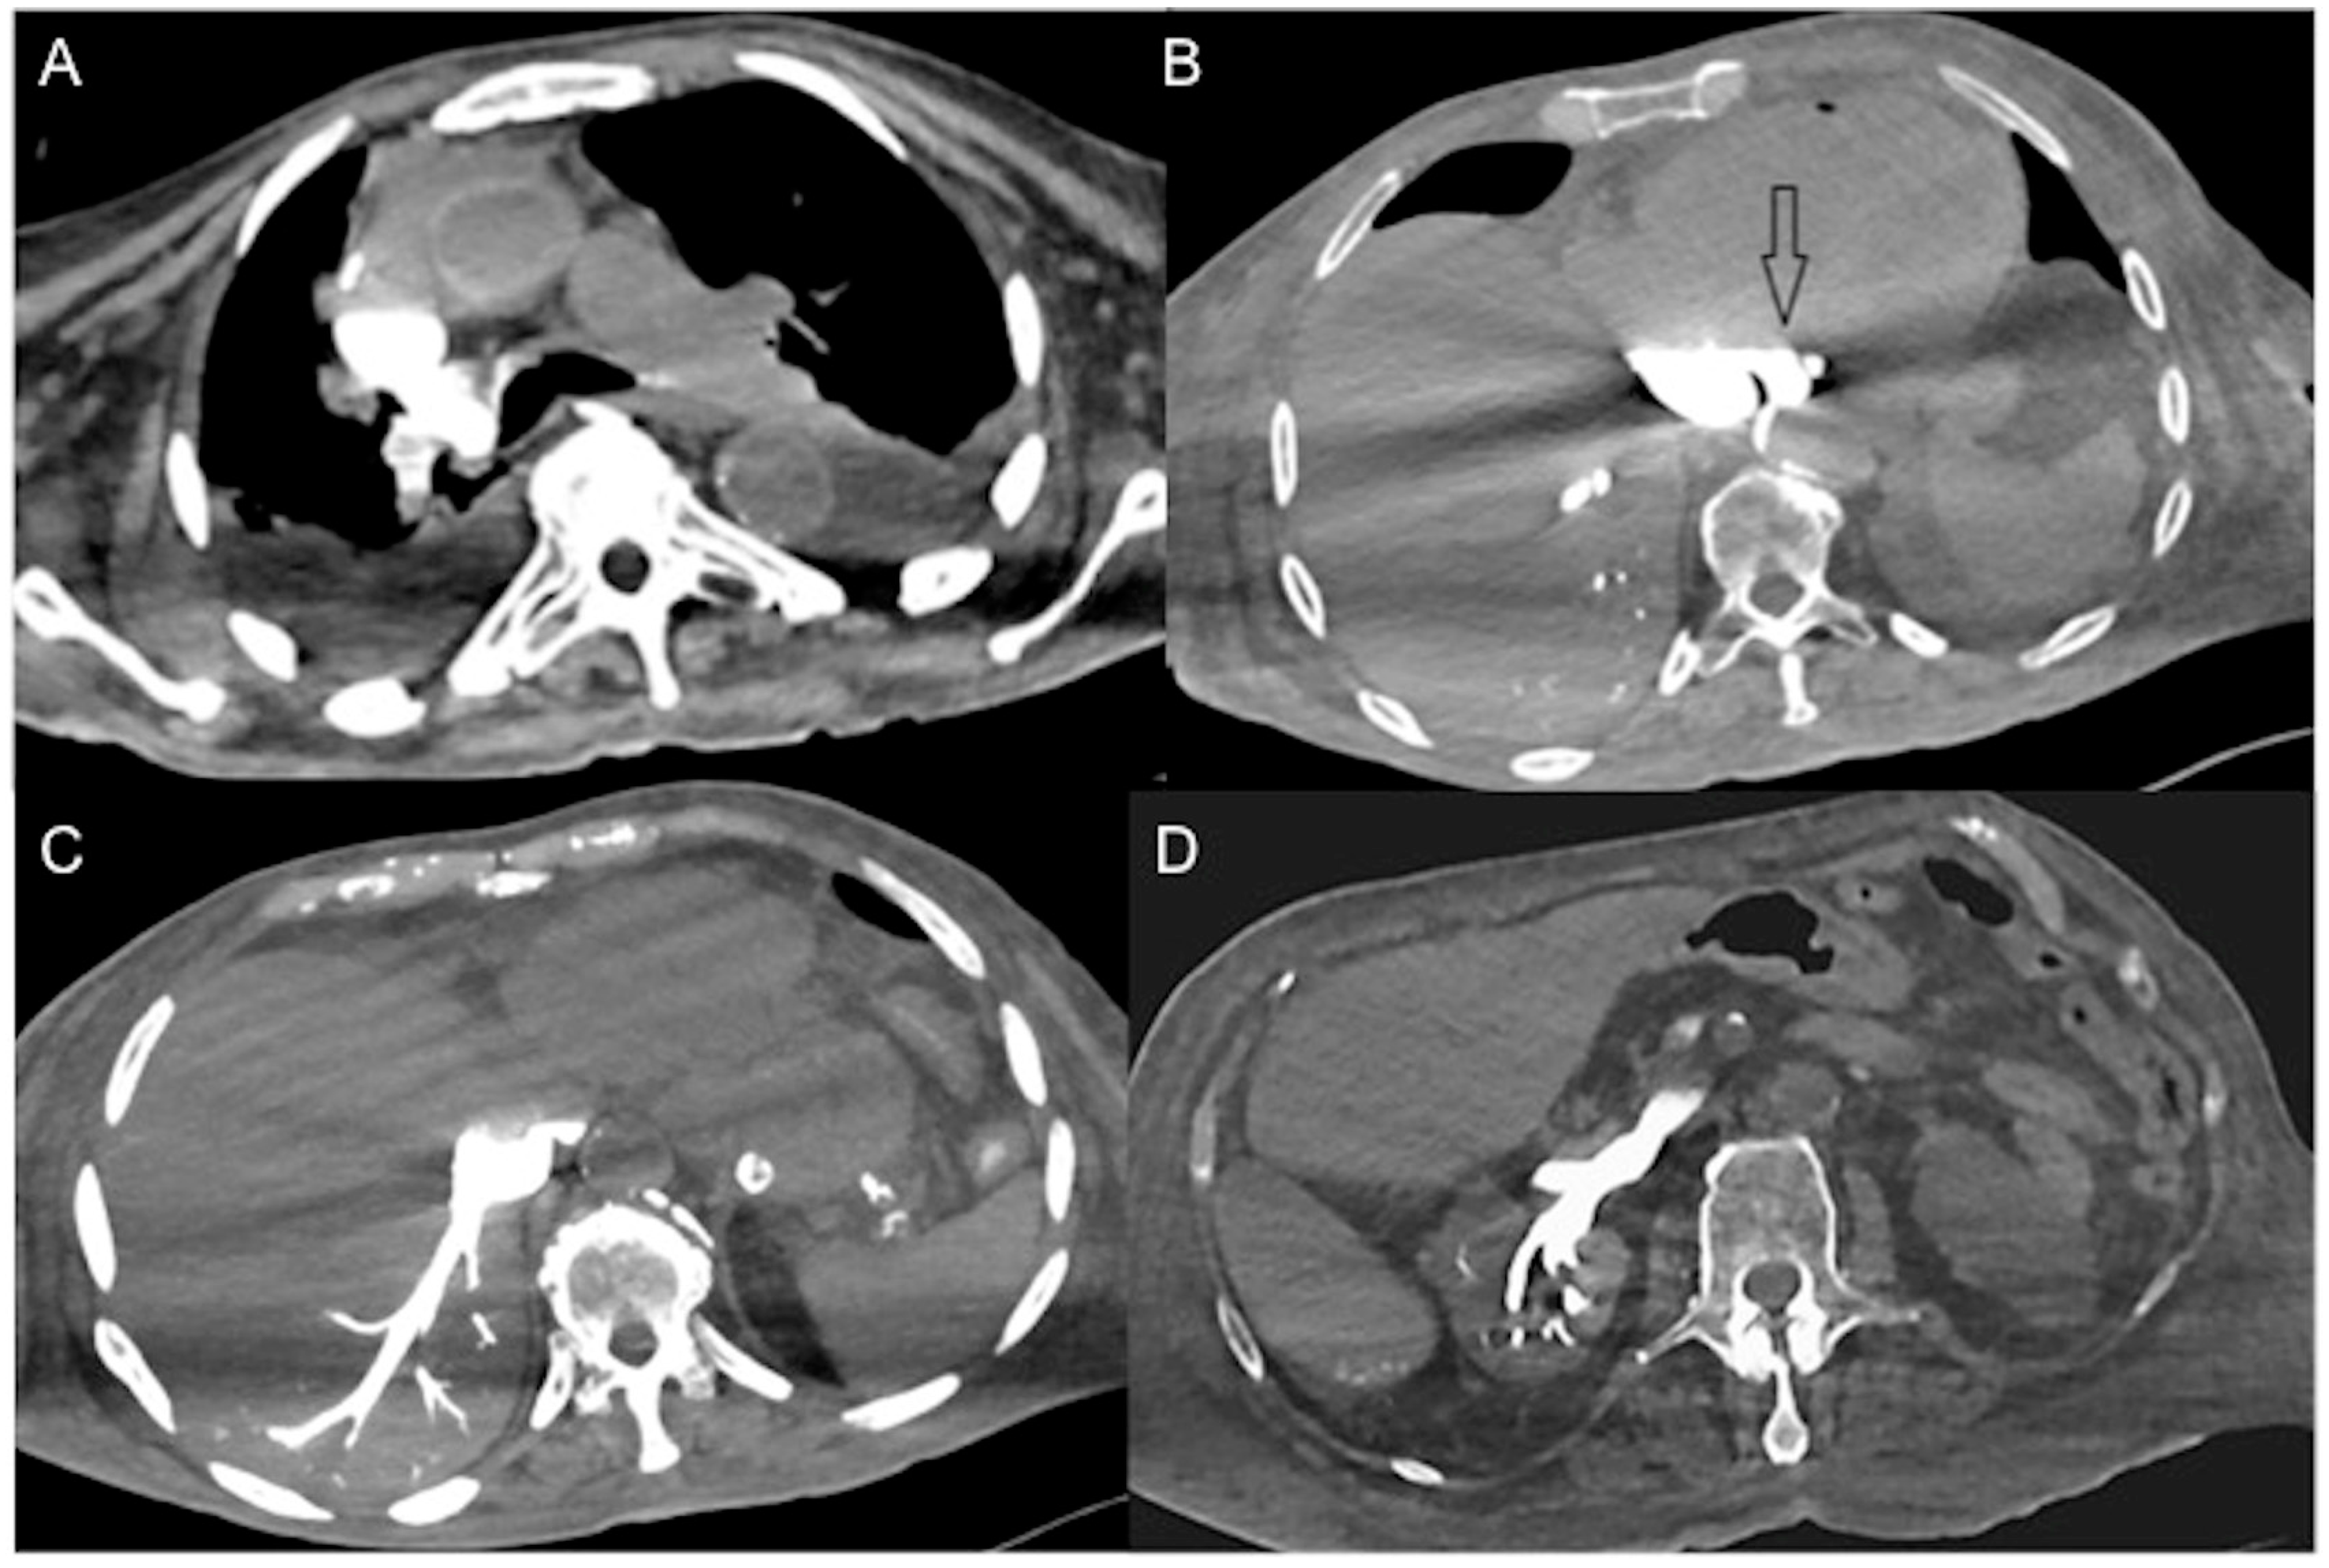

- In irreversible end-organ dysfunction, injected IV CM circulation is supported only by the pressure applied by the automated power injector and the density of contrast material. Circulatory arrest leads to dense contrast pooling and layering in the SVC, IVC (inferior vena cava), and right heart chambers with non-opacified left heart chambers or arterial vessels (Figure 1) [43,45,49,50,51,52]. This may be called the “non-beating heart” pattern. Cardio-pulmonary aggressive resuscitation must immediately be initiated within the framework of a predetermined emergency plan.

Figure 1. Non-beating heart in a 72-year-old man with sudden-onset severe dyspnea/shock and asystole during thoraco-abdominal CT. (A) CECT axial image shows dense contrast in the round superior vena cava, and reflux in the azygous arch; (B) contrast pooling and layering in the right atrium and IVC with retrograde opacification of coronary sinus (arrow). (C) CM fills the round inferior vena cava with hypostatic reflux into the hepatic veins, hemiazygos vein, partially splenic vein, and (D) right renal vein. Note no mixing of blood with CM and no opacification of the pulmonary arteries, aorta, and left cardiac chambers, suggestive of a non-beating heart. Prompt initiation of cardio-pulmonary resuscitation to restore circulation was useless. Autopsy: ruptured myocardial infarction.